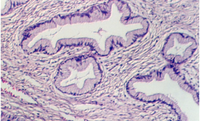

Stratified Columnar epithelium is rare. One place you can find it is in the largest ducts of salivary glands (parotid, submandibular, etc). The basal layer of cells are cuboidal cells and the layer nearest the apical surface includes columnar cells. The large droplets are mucus, in Goblet cells. This also illustrates the fact that epithelia are classified according to the cells nearest the lumen, in this case columnar.

Below is another view of a large (excretory) duct of a salivary gland showing the mucin in Goblet cells after a special stain. What might be the advantages of an epithelium that has a basal cuboidal cell layer and an apical columnar cell layer?